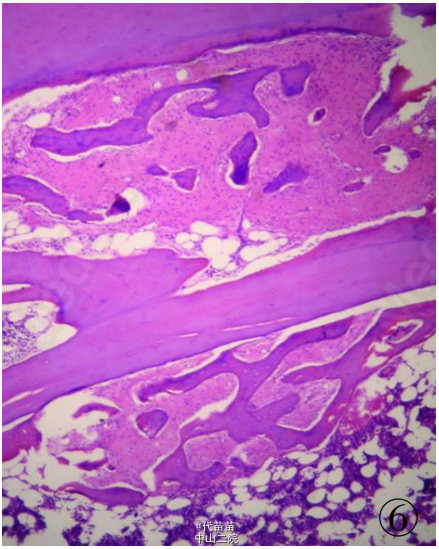

患者男性,40 岁。因体检发现肋骨肿块入院。患者无其它特殊症状,血生化检查基本正常,无放、 化疗史及Paget病史。CT检查示右侧第九后肋骨旁一团块状混杂高密度影,肿块边界尚清,位于肋骨表面,非髓内生长,向胸腔隆起,位于壁层胸膜与肋骨之间,与骨皮质有蒂相连(图 1、2)。临床考虑良性病变骨软骨瘤可能,遂行手术切除一段肋骨及表面肿块,送病理检查。 病理检查:眼观:送检肋骨1段,长9cm,宽2cm,骨表面隆起卵圆形肿块,4 cmX2 cmX2 cm 大小,质硬,切面灰白色,实性,与骨皮质有蒂相连,蒂部骨皮质浸润(图 3)。镜检:肿瘤由大量狭长且具平行排列倾向的高分化骨小梁构成,以编织骨为主,部分骨小梁已成熟为板层骨,大部分骨小梁周围缺乏成骨细胞被覆,部分区域已逐渐移行为有成骨细胞被覆的板层骨,瘤骨内可见骨重建过程中形成的粘合线,即所谓“Paget” 现象(图 4)。骨小梁间充满低细胞性纤维组织间质,梭形成纤维细胞形态温和,细胞核卵圆形,缺乏不典型性,部分肿瘤性骨小梁之间有脂肪髓形成,但无造血组织。肿瘤表面的骨样组织较幼稚,深部为相对成熟的粗大编织骨和板层骨(图 5),蒂部皮质和近皮质的髓腔内有局灶性肿瘤浸润(图 6)。肿瘤内含多灶性高分化软骨,软骨细胞排列紊 乱无极性,由于部分软骨位于肿瘤表面,故影像学和病理学类似骨软骨瘤改变。病理诊断:右侧第九后肋骨旁骨肉瘤。 骨旁骨肉瘤临床表现为骨表面缓慢生长的无痛性肿块,质硬,病程较长,可达数年。骨旁骨肉瘤预后较好,其5 年生存率达91% ,最佳治疗方案是大块肿瘤完整切除,切除范围应包括肿瘤周围的正常组织和软组织内的卫星病灶。若不完整切除则很容易复发。复发性肿瘤易发生去分化改变,称去分化骨旁骨肉瘤,其预后类普通型骨肉瘤,治疗原则和普通高级别骨肉瘤一致。 骨旁骨肉瘤可以说是骨肉瘤中的“异类” ,因为其不仅分化好,类似良性骨病,而且在骨表面生长,在病理诊断时须注意与以下三种良性骨病鉴别:(1)纤维结构不良。本例虽然部分肿瘤性编织骨呈不连续的字母状结构,在编织骨之间为高分化纤维,类似于纤维结构不良,但纤维结构不良是一 种纤维化生骨,伴有骨的成熟障碍,不会成熟为板层骨,也不会出现板层结构瘤骨在改建塑型过程中形成“Paget”现象。本例镜下见瘤骨比较成熟、 粗大,大部分相互连接成网,并有平行排列倾向,肿瘤表面骨样组织幼稚,深部较为成熟,并形成板层骨,成熟瘤骨内能见到“ 孕葬早藻贼” 现象。此外纤维结构不良均在髓内生长,不会在骨表面外生性生长,故影像学改变即可排除纤维结构不良。(2)骨软骨瘤。本例肿瘤内含有少量高分化软骨组织,由于部分软骨位于肿瘤表面,需与骨软骨瘤鉴别。骨软骨瘤蒂部的骨皮质常有缺损,肿瘤内的松质骨与宿主骨的正常松质骨相连续,二者相互融合。而骨旁骨肉瘤常环绕宿主骨在骨膜外生长,与髓腔不相通,肿瘤与骨密质之间有狭长的透亮带,即残存的骨膜;骨软骨瘤软骨帽下是由软骨化骨形成的松质骨小梁,骨小梁间隙内充满正常的造血性红髓或脂肪性黄髓,而缺乏骨旁骨肉瘤的成纤维细胞成分。同时骨旁骨肉瘤内的软骨组织、 结构和分布随意紊乱,缺乏骨软骨瘤明显的分层结构。(3)骨旁骨瘤。大多位于颅骨表面或副鼻窦内,分化成熟的骨小梁之间为脂肪细胞和小血管,缺乏纤维母细胞性间质。